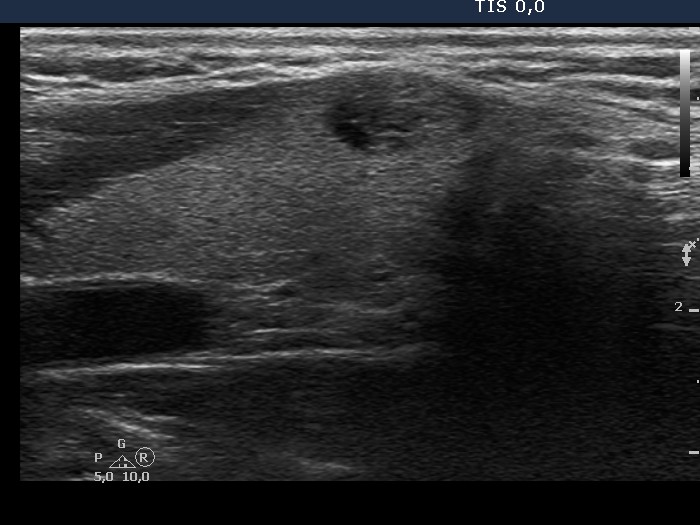

Ultrasonography. There was a mixed solid cystic nodule in the right side of the isthmus. Otherwise, the thyroid was intact.